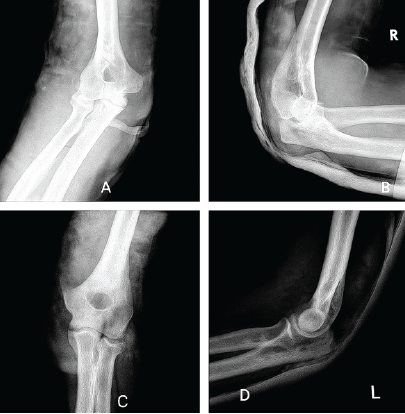

A 42-year-old right-handed male construction worker fell from a scaffold approximately 10 feet high. He landed with both arms outstretched and elbows extended. Upon presentation, the patient had gross deformity, pain, and swelling at both wrists and elbows. Upon inspection, deformities were seen on both wrists and elbows bilaterally. On examination, tenderness was found with a limited range of motion. Neurovascularity was intact in both upper limbs. X-rays revealed bilateral posterior elbow dislocation without associated fracture (Fig. 1a, b, c, d) and bilateral comminuted intra-articular distal radius fractures (AO 23-C2). (Fig. 2a, b, c, d). In the emergency setting, both elbow dislocations were promptly managed with closed reduction under sedation, and concentric reduction was confirmed on post-reduction radiographs (Fig. 3a, b, c, d). Both wrists were also reduced, and stabilization was done with slab application (Fig. 4a, b, c, d). Following initial stabilization and resolution of soft tissue swelling, the patient underwent staged open reduction and internal fixation of the bilateral distal radius fractures using a volar approach (modified Henry technique). Fixation was achieved using volar locking compression plates for both wrists (Fig. 5a, b, c, d).

Figure 3: Post-reduction X-rays of the right elbow in anteroposterior (a) and lateral (b) view and left elbow in anteroposterior (c) and lateral (d) view.